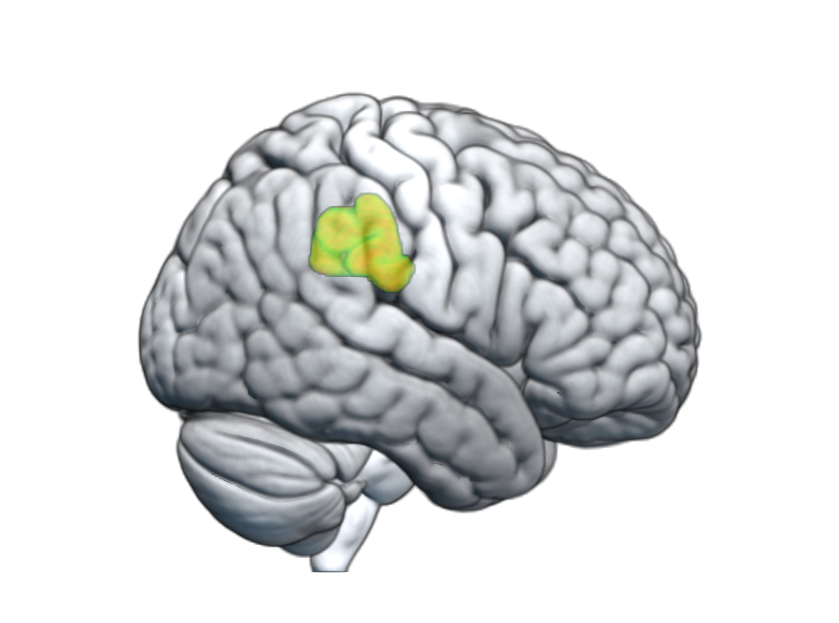

Hasta ahora, la lentitud motora se trataba como un síntoma clínico, pero esta investigación va más allá al demostrar que existe un déficit en el procesamiento sensorial. Los resultados indican que la reducción de los pliegues corticales afecta a regiones críticas del cerebro encargadas de procesar la información necesaria para ejecutar movimientos. En otras palabras, el cerebro tiene más dificultades para procesar la información necesaria para ejecutar acciones que antes eran automáticas.

Este hallazgo es vital para entender la enfermedad. Como explica el Dr. Antoni Callén, neurólogo del Hospital SJD Sant Boi, entender que hay una base estructural ayuda a comprender la frustración y el esfuerzo extraordinario que experimentan los pacientes para llevar a cabo tareas "sencillas". No es solo lentitud; es un cerebro trabajando contra una estructura que ha cambiado.

- Resonancias magnéticas como biomarcador: Las pruebas de imagen podrían convertirse en la herramienta definitiva para detectar cambios precoces en el córtex.